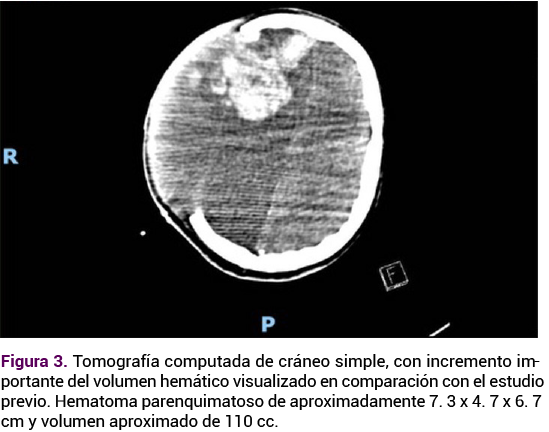

Paciente de 39 años, con antecedentes de artritis reumatoide en remisión, dos embarazos y una cesárea, en curso de las 14.1 semanas de la gestación actual, establecidas con base en la fecha de la última menstruación. Acudió a urgencias debido a un cuadro de cefalea pulsátil 10/10 según la escala verbal numérica, de inicio súbito, de 30 minutos de evolución, acompañada de náusea y vómito de contenido gástrico. Posterior a su ingreso tuvo pérdida de la conciencia y crisis convulsivas, con estado epiléptico, que ameritaron maniobras avanzadas en la vía aérea. La exploración física se valoró con la escala de coma de Glasgow 5 (O:1, V:1, M:3), pupilas anisocóricas a expensas de midriasis derecha de 5 mm e izquierda de 2 mm, abdomen globoso a expensas del embarazo. La TAC simple de cráneo reportó una extensa zona de hemorragia frontotemporal derecha, con edema periférico que provocaba el desplazamiento por efecto de masa de la cisura interhemisférica y compresión del sistema ventricular supratentorial. Luego de la interconsulta con el neurocirujano, neurólogo y obstetra se procedió a la craniectomía descompresiva, drenaje del hematoma subdural e intracerebral y la plastia dural.

<strong>Figura 1</strong>

Figura 1. TAC simple de cráneo. Extensa zona de hemorragia frontotemporal derecha, con edema periférico que provocaba el desplazamiento por efecto de masa de la cisura interhemisférica y compresión del sistema ventricular supratentorial.